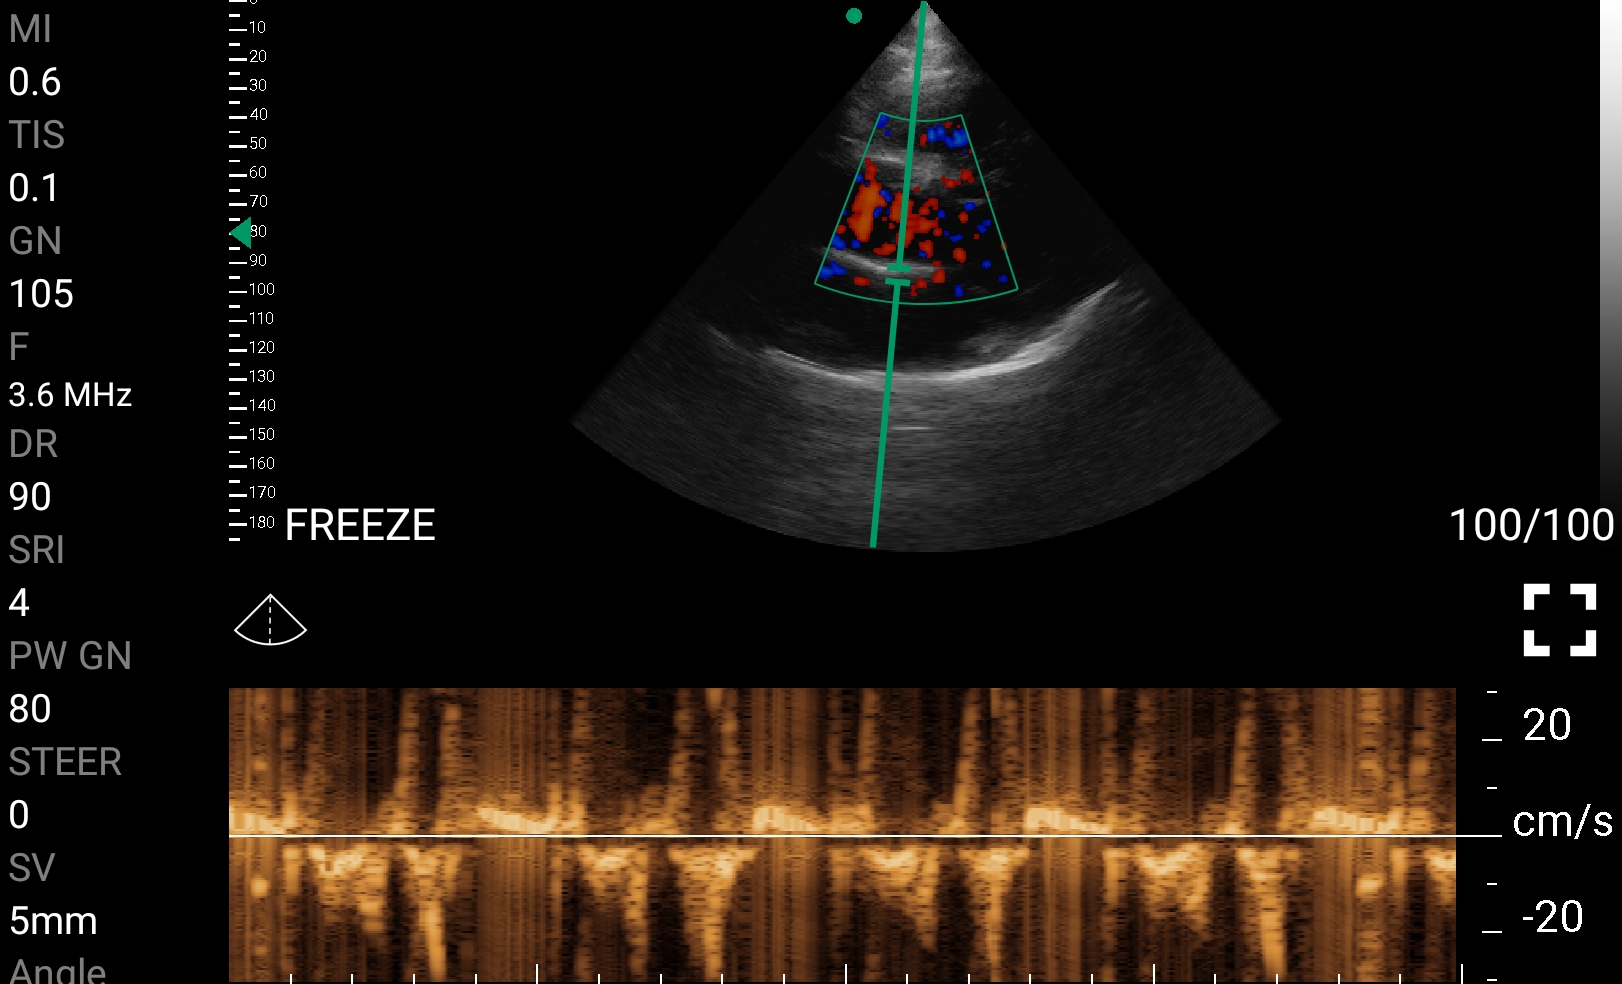

• Doppler καρδιακών βαλβίδων: Βασική εκτίμηση στένωσης/ανεπάρκειας.

Ολες οι παραπάνω απεικονιστικές εξετάσεις έχουν ληφθεί από φορητή συσκευή όπως: Apple Iphone, Tablet, Samsung Mobile Phones και διάφορες άλλες φορητές συσκευές.

• Echocardiography: Ταχεία εκτίμηση της καρδιακής λειτουργίας σε ασθενείς με υπόταση ή ανακοπή.

Παραδείγματα Video